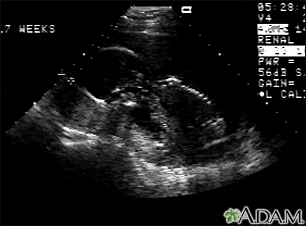

Ultrasound, normal fetus - profile viewBackUltrasound, normal fetus - profile viewThis is a normal fetal ultrasound performed at 17 weeks gestation. In the middle of the screen, the profile of the fetus is visible. The outline of the head can be seen in the left middle of the screen with the face down and the body in the fetal position extending to the lower right of the head. The outline of the spine can be seen on the right middle side of the screen. E-mail FormEmail ResultsName:Email address:Recipients Name:Recipients address:Message: